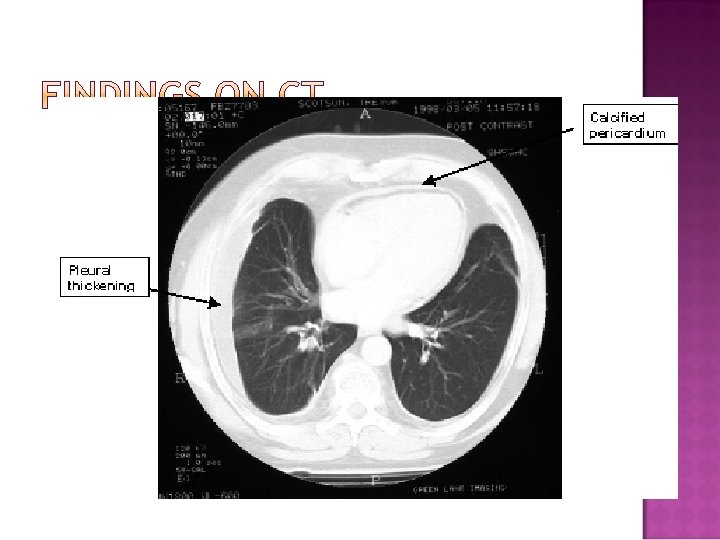

� Tamponade � Other is a Clinical Diagnosis Detection Methods �EKG �CXR �TTE �R Heart Cath �CT, MRI